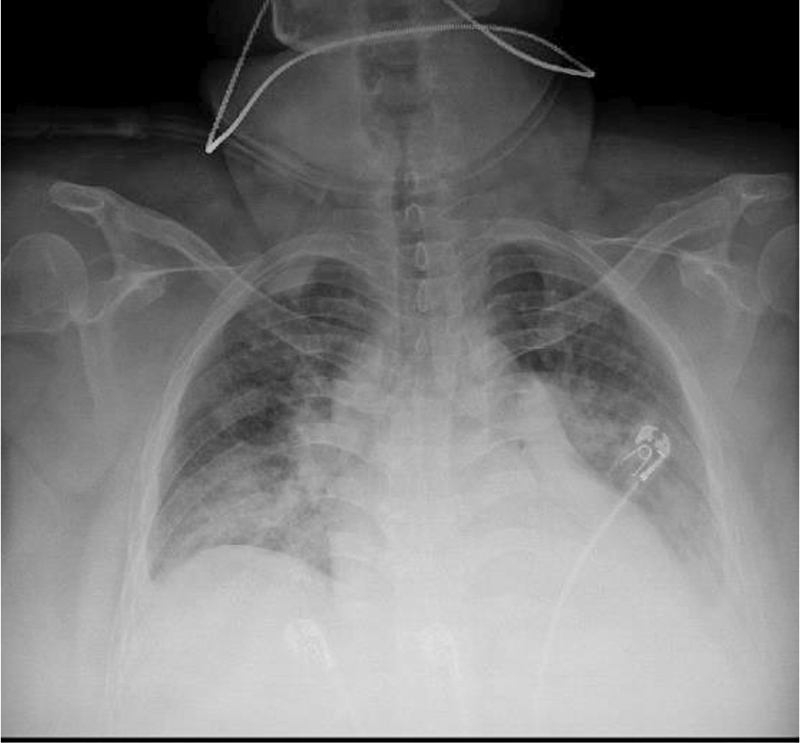

On day 3 of hospitalization, the patient’s fever was 102.3F, and she was started on azithromycin 500 mg IV daily. A repeat chest x-ray revealed retrocardiac opacity, suggesting infectious process (Figure 1). The patient now required 3L by nasal cannula (NC) from room air. Overnight, the patient was found to be tachycardic once again at 118 beats/min, febrile with temperature recorded at 102.9F, and worsening oxygenation increasing from 3L of NC to 15L on a non-rebreather mask saturating 88%. A commuted tomography (CT) of the chest was done to rule out PE; a physical exam noted crackles in bilateral lung fields, and the patient was administered IV Lasix 20 mg. She was also up titrated to high flow nasal cannula at 40L O2 and 60% of FiO2. A chest CT was negative for pulmonary embolism but did reveal bilateral extensive pulmonary consolidations affecting all lobes but most severely involving bilateral lower lobes, consistent with multifocal pneumonia as well as trace bilateral pleural effusions (Figure 2).

Figure 2

Figure 2. CTA Chest (PE Protocol), indicating extensive bilateral pulmonary consolidations affecting all bilateral lobes consistent with multifocal pneumonia.